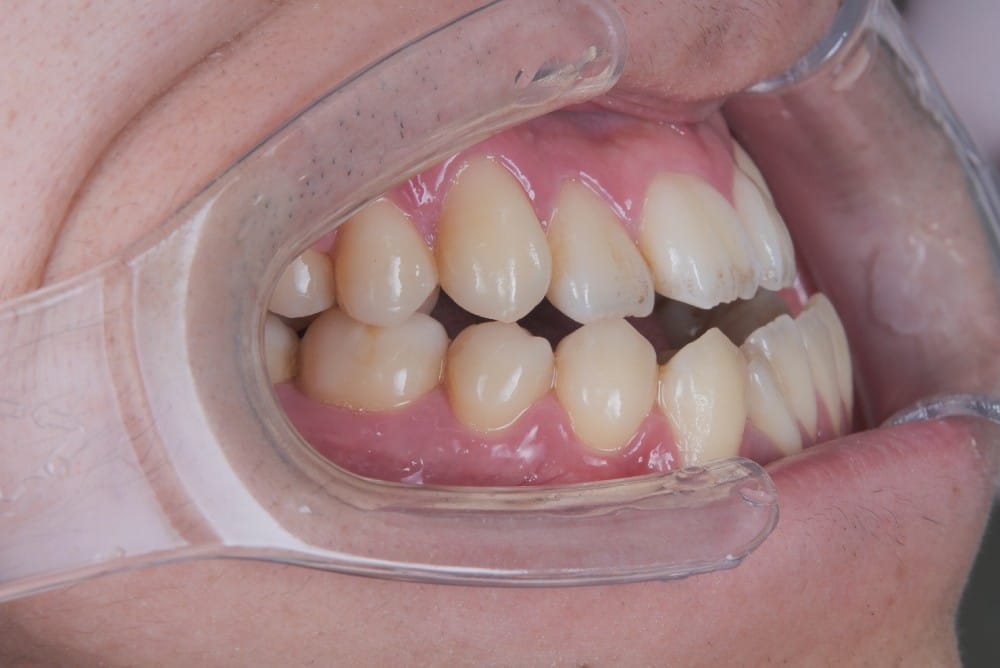

30代の女性で、受け口とガタガタを主訴にご来院されました。

治療前

分析しますと

- 骨格的な上下あごの前後差は中等度〜重度

- 噛み合わせの位置も下あごの奥歯が半分くらい前にズレていた

- 上の前歯が内側に傾斜している

というケースで、外科的な処置も検討するようなケースでした。

骨格的なズレや奥歯の噛み合わせのズレもあり、重度の受け口でしたが、上あごの前歯が内側に傾斜しているため、本来の歯の軸に戻すことで、受け口を改善できると診断し、治療を開始しました。

先ほどのケースと同じように、患者さまに外科的な手術の選択肢も提示しましたが、希望されず、横顔の変化はおそらく起こらないことを納得の上、治療をスタートいたしました。

今回のケースも奥歯の移動量が大きいため、マウスピースだけでは難しいと判断し、カリエールとよばれる装置を補助的に使用し、上下の噛み合わせの前後関係を整えることで、手術を行わずに機能面と見た目の両方が改善することにしました。

治療中の直近の写真です。生まれつき小さな歯である前から両側の2番目の歯は、被せ物をして見た目の回復をする予定にしています。

<治療前と現在の比較です>

矯正治療によって前歯の被さりを改善することで、先ほどの症例ほどではありませんが、下唇の突出感が減り、上唇も正常な位置に戻り、横顔がやわらかい印象に変化しました。